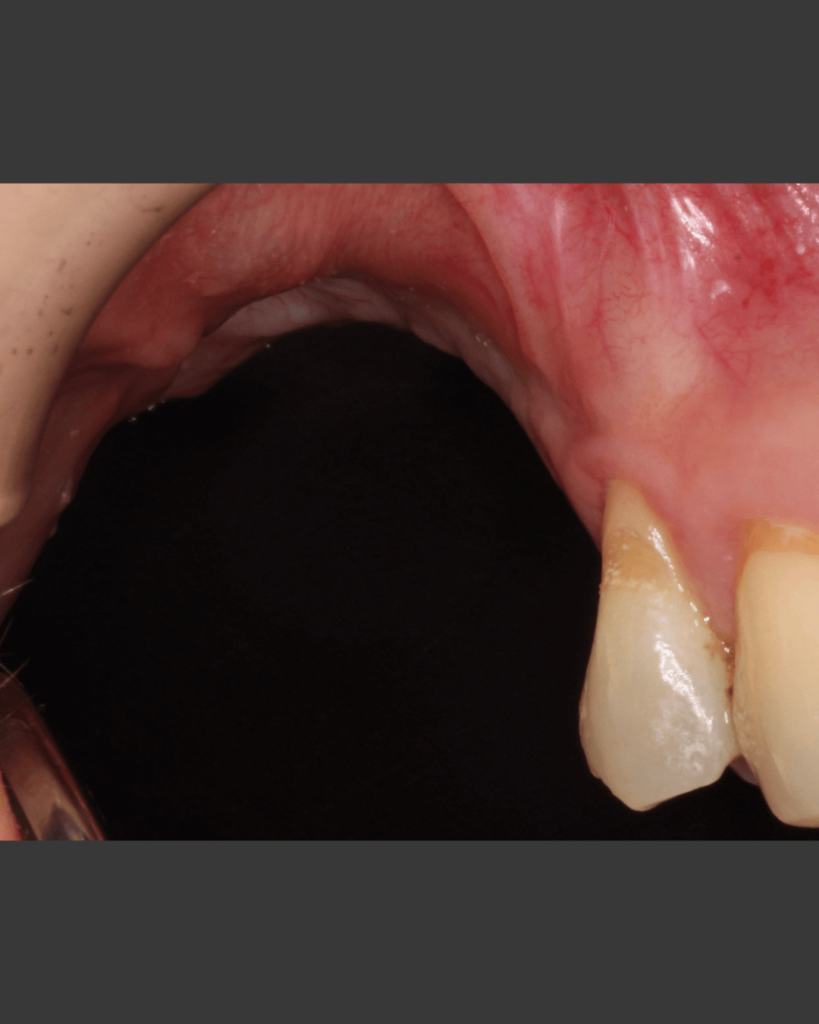

Klinischer Fall

NeoGen® Cape PTFE-Membran, fixiert auf einem gleichzeitig eingesetzten Implantat.

Nach 3 Jahren Entwicklungszeit stellen wir Ihnen die neu entwickelte NeoGen Cape PTFE-Membran vor. Besonders in Fällen von bukkalem Knochendefizit in der ästhetischen Zone ist diese innovative Fixierungsmethode eine hervorragende Lösung für die Behandlung solcher Fälle.

Nachweis einer vertikalen Kieferkammaugmentation bei gleichzeitiger Implantation

Die einzigartige Konstruktion der NeoGen Membranen ermöglicht herausragende klinische Ergebnisse, einschließlich reproduzierbarer und vorhersagbarer Ergebnisse für die anspruchsvolle Indikation der vertikalen Kieferkammaugmentation.